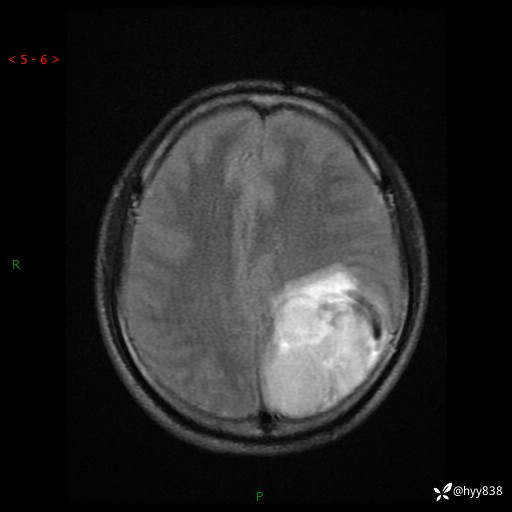

病例年轻小伙,头痛伴呕吐半年,渐进性加重1月。疑难病例,第一次见--结果公布~

性别:男

年龄:21岁

简要病史:头痛伴呕吐半年,渐进性加重1月

颅脑MRI平扫+增强